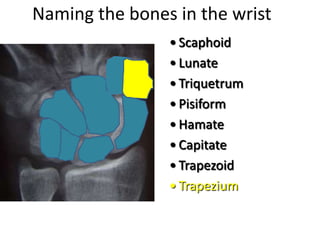

- Naming the bones, joints, tendons, nerves and skin landmarks of the hand and wrist.